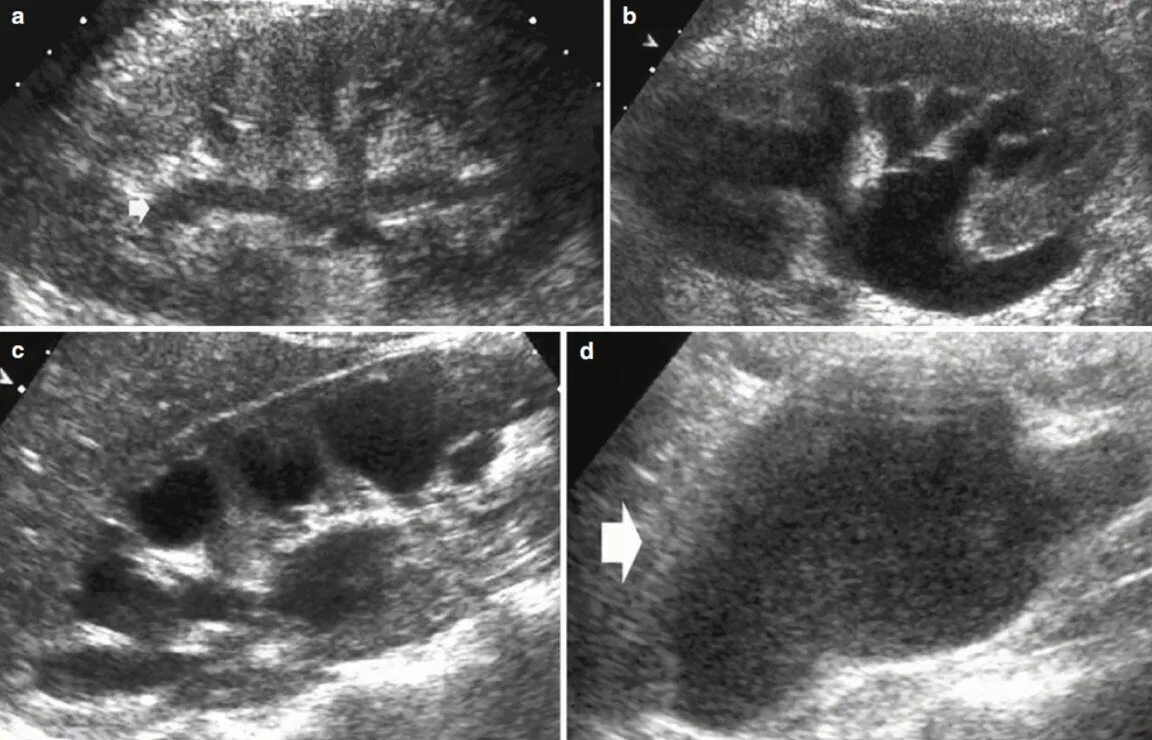

Диффузные изменения члс